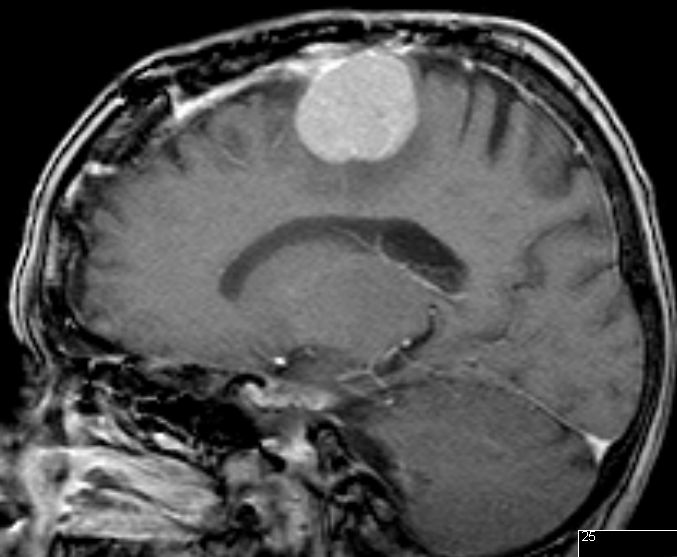

| zurück Home | Meningeom parietal | |||

72-jährige Patientin mit Teilparese des rechten Beins, passageren Sprachstörungen und Krampfanfall vor 6 Monaten. | |||

Postoperative Histologie: Meningeom Grad 1 | . | ||

Rezidiv 2 Jahre später. Postoperative Histologie: atypisches Meningeom II°![]() |